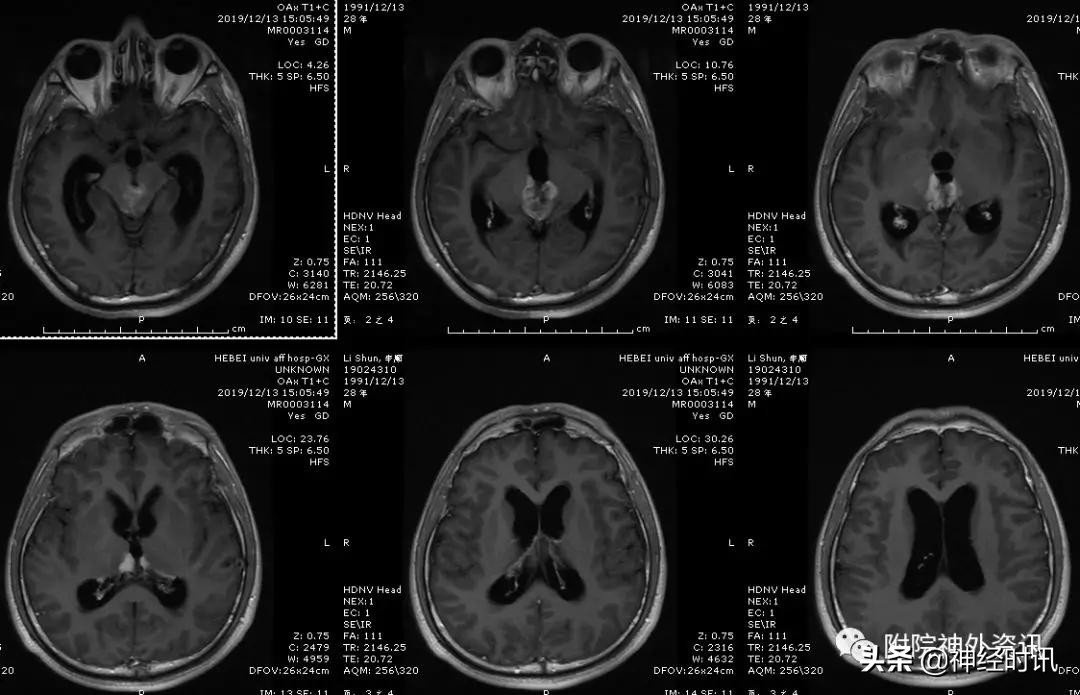

生殖细胞瘤强化明显,边界清楚,沿着第三脑室侧壁生长,形成所谓的“蝶形征”。

男性,28岁,主因复视20余天入院,查体双瞳孔不等大,直径左=3. 5mm,右=3.0 mm,对光反射迟钝,双眼上视困难,左眼眼位异常,向内下斜视。